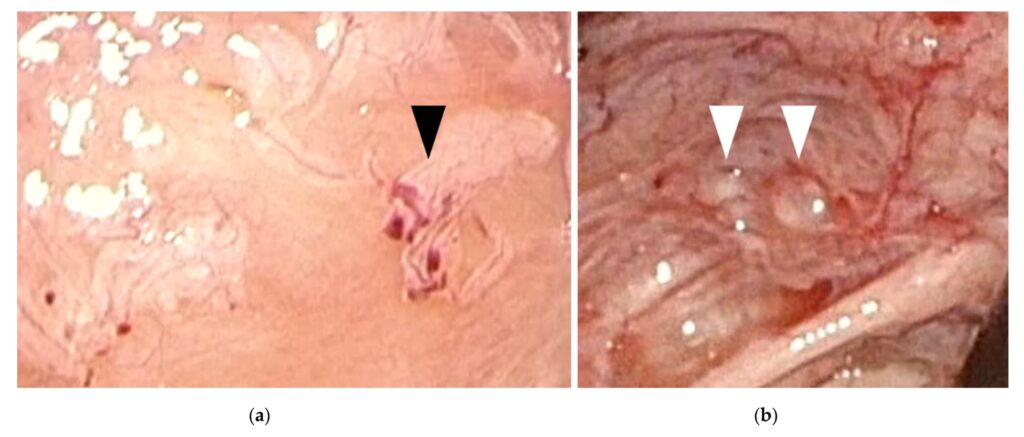

Diagnosen starter med en grundig samtale om dine symptomer og en gynækologisk undersøgelse. En ultralydsscanning kan nogle gange vise endometriose-cyster på æggestokkene, men den kan ikke se de flade læsioner på bughinden. Den eneste sikre måde at stille diagnosen på er ved en kikkertoperation (laparoskopi), hvor en kirurg kan se direkte ind i bughulen. Læger vil dog ofte starte behandling baseret på en stærk mistanke ud fra symptomerne for at undgå en operation.